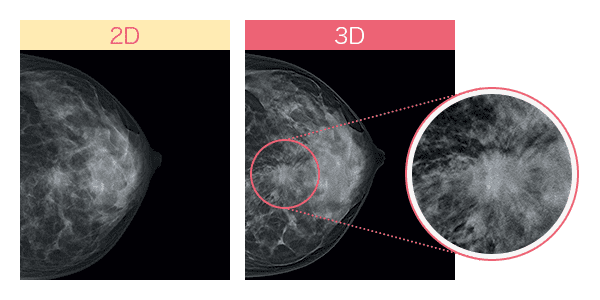

従来のマンモグラフィ画像は、平面の撮影(2D)のため乳腺と病変が重なると、判別が難しく正確な診断に時間を要することがあります。

しかし最近では乳房内の構造をより正確に描出できる「3Dマンモグラフィ(トモシンセシス)」が登場して、より高い精度で乳がん検査を行うことが可能になりました。異なる角度から乳房の画像を複数撮影し、それを再構成して乳房の断層像を生成することで、乳腺の重なりが除外でき、これまで発見が難しかった病変の観察がしやすくなりました。*4